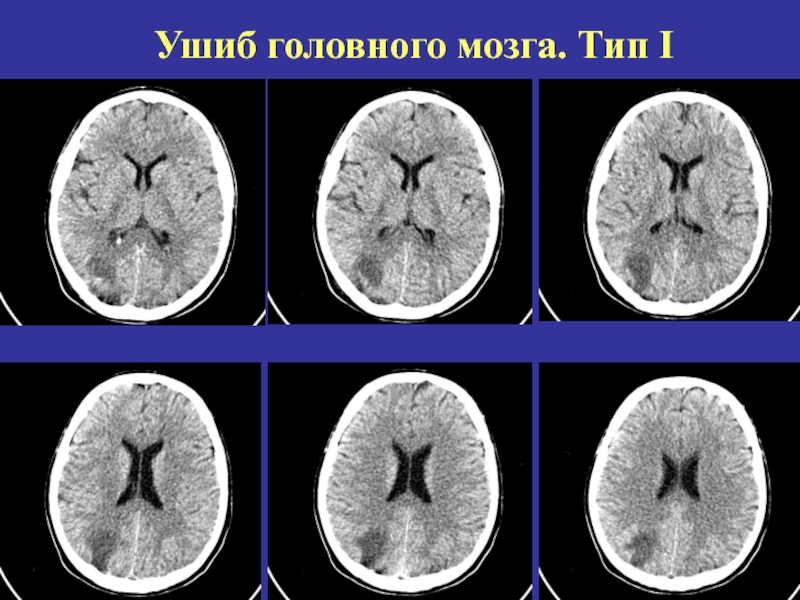

Слайд 24Ушиб головного мозга. Тип I

Ушиб головного мозга. Тип I

Слайд 22Классификация ушибов головного мозга при КТ (Корниенко В.Н, Васин Н.Я., Кузьменко

В.А., 1987 г.)

1.Ушиб 1 вида-зоны пониженной плотности вещества головного мозга

(+18-25 HU)

2.Ушиб 2 вида- очаги контузионного повреждения мозга, проявляющихся в одних случаях некомпактным расположением высокоплотных мелкоточечных включений в зоне пониженной плотности, в других – умеренным повышением плотности в очаге ушиба до 50HU.

3.Ушибы 3 типа- зоны неоднородного повышения плотности мозгового вещества (+64-76 HU)

4.Ушибы 4 типа- одиночные или множественные, массивные, округлой или овальной формы очагами интенсивного гомогенного повышения плотности от +64 до +76 HU

Классификация ушибов головного мозга при КТ (Корниенко В.Н, Васин Н.Я., Кузьменко В.А., 1987 г.)1.Ушиб 1 вида-зоны пониженной